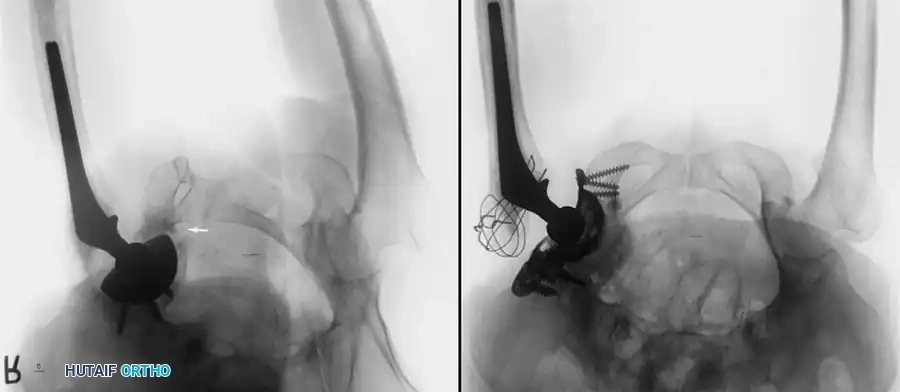

Acetabular Extraction

Removal of a well-fixed cementless acetabular component can result in catastrophic bone loss if not performed meticulously. The use of curved, flexible osteotomes (e.g., the Explant system) allows the surgeon to cut the bone-implant interface precisely along the hemisphere of the cup, preserving the critical subchondral bone of the acetabular dome and columns.

* Cementless Stems: Well-fixed porous-coated stems require disruption of the osteointegrated interface. Flexible osteotomes and high-speed pencil burrs are used to clear the proximal shoulder. If the stem cannot be extracted with a universal slap-hammer, an ETO must be performed to prevent iatrogenic proximal femur fracture.

RECONSTRUCTION AND REIMPLANTATION

Acetabular Reconstruction

The goal of acetabular revision is to restore the anatomic center of rotation, achieve rigid initial fixation, and provide a biologic environment for long-term stability. Defects are classified using the Paprosky system.

- Type I & II Defects (Cavitary): Managed with hemispherical, highly porous-coated "jumbo" cups (typically >62 mm) and particulate cancellous autograft/allograft. Multiple screws are utilized in the safe zone (posterosuperior quadrant) to achieve rigid primary fixation.

- Type III Defects (Segmental/Severe): Require advanced techniques. Trabecular metal augments are used to fill superior segmental defects and support the cup. In cases of pelvic discontinuity, a cup-cage construct or custom triflange acetabular component may be necessary.